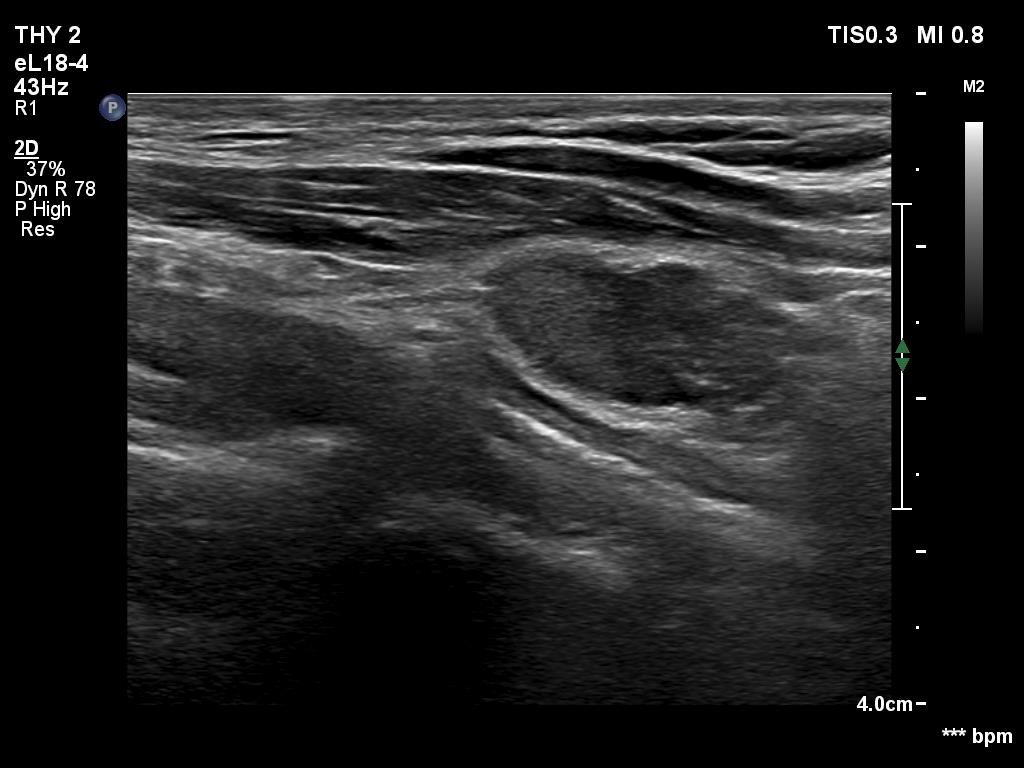

Follow-up examination 8 years later (4th and 5th rows of images):

Ultrasonography revealed hypoechoic discrete lesions in both thyroid lobes. The lesions presented microcalcifications. Corresponding to the palpable mass in the right submandibular region, a reactive-type regular lymph node was found. There was an enlarged lymph node in the left submandibular region. The node had a regular hilum but displayed a heterogeneous pattern.

Cytology was performed from both lymph nodes and from the lesion in the left thyroid bed. FNA resulted in non-diagnostic report from the lesion in the left thyroid bed while cytology of the submandibular lymph nodes showed patterns of a benign, reactive-type lymph node.

Wash-out thyroglobulin levels were 0, 81.1 and 104.9 ng/mL, right submandibular lymph node, left thyroid bed lesion and left submandibular lymph node, respectively.

Histopathology in progress.

Comment. Until the final histological examination is completed, I would like to draw attention to two things. One is the heterogeneity of the left lymph node and the other is the size and structure of the lesions in the thyroid beds - these features are suspicious of thyroid cancer.